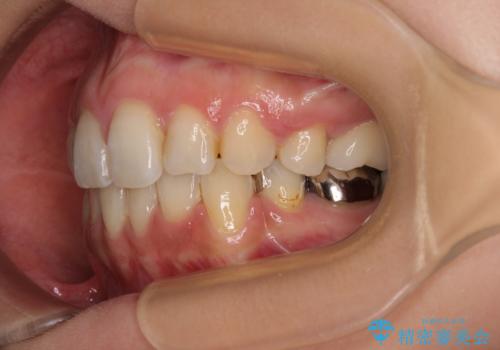

デコボコと口元の突出感 ハーフリンガルでの抜歯矯正

- 前歯のデコボコと上顎の前突感による口の閉じにくさを気にして来院された患者様です。

目立たない装置を希望されたので、上顎が裏側装置のハーフリンガルを選択し、上下左右の小臼歯(計4歯)を抜歯して矯正治療を行うこととしました。